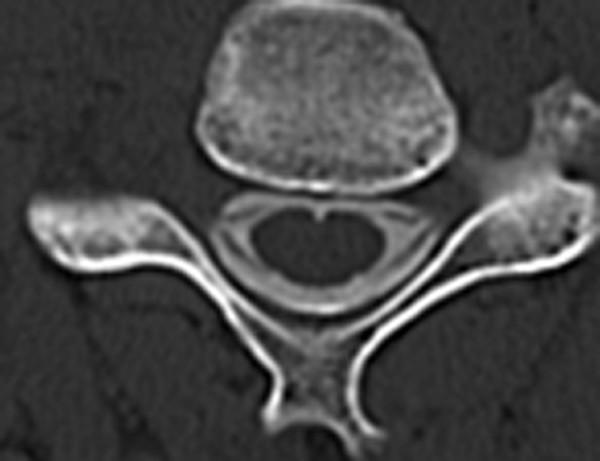

The authors describe a new computerized tomography (CT) myelography technique with coronal and oblique coronal view to demonstrate the status of the cervical nerve rootlets involved in brachial plexus injury. They discuss the value of this technique for diagnosis of nerve root avulsion compared with CT myelography with axial view.

CT myelography was performed with penetration of the cervical subarachnoid space by the contrast medium. Then the coronal and oblique coronal reconstructions were created. The results of CT myelography were evaluated and classified with presence of pseudomeningocele, intradural ventral nerve rootlets, and intradural dorsal nerve rootlets. The diagnosis was by extraspinal surgical exploration with or without spinal evoked potential measurements and choline acetyl transferase activity measurement in 25 patients and recovery by a natural course in 3 patients. Its diagnostic accuracy was compared with that of CT myelography with axial view, correlated with surgical findings or a natural course in 57 cervical roots in 28 patients.

Coronal and oblique coronal views were superior to axial views in visualization of the rootlets and orientation of the exact level of the root. Sensitivity and specificity for coronal and oblique coronal views of unrecognition of intradural ventral and dorsal nerve root shadow without pseudomeningocele in determining pre-ganglionic injury were 100% and 96%, respectively. There was no statistically significant difference between coronal and oblique coronal views and axial views.

The information by the coronal and oblique coronal slice CT myelography enabled the authors to assess the rootlets of the brachial plexus and provided valuable data for helping to decide whether to proceed with exploration, nerve repair, primary reconstruction.